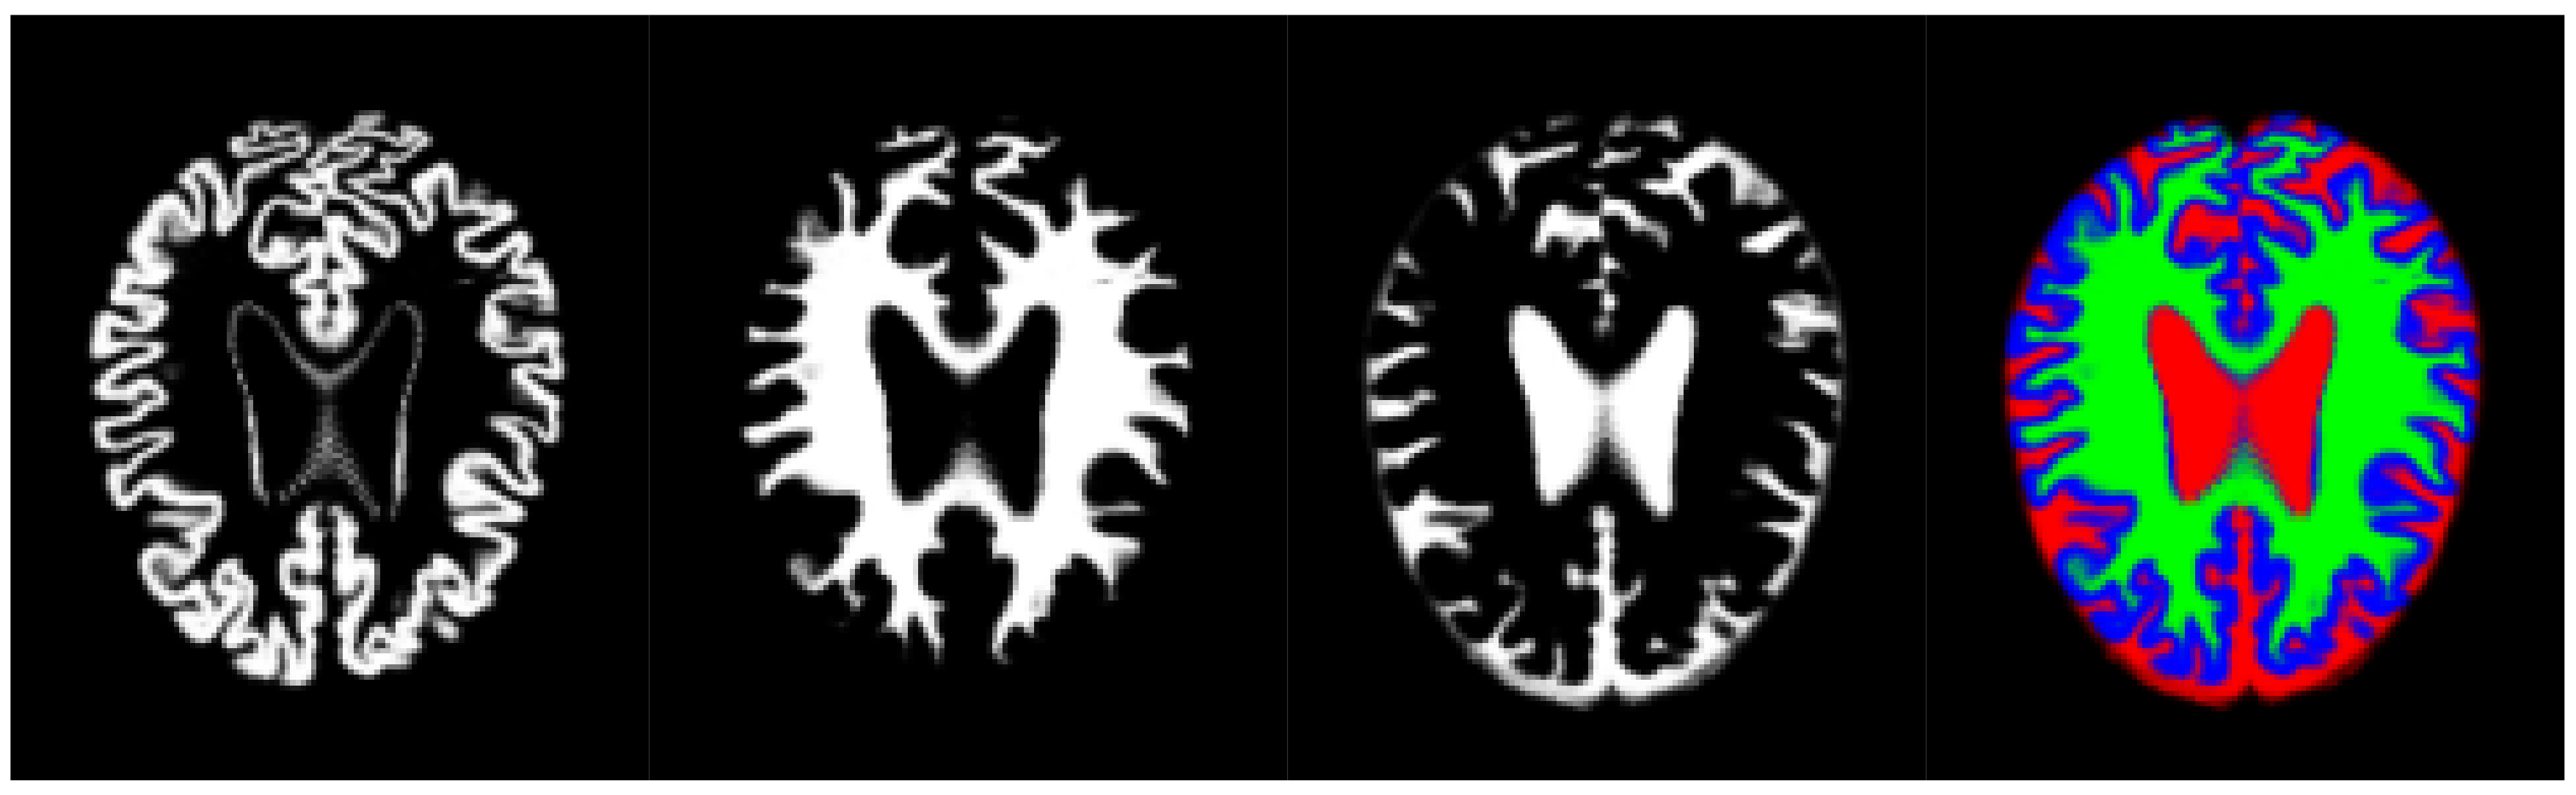

Thus, we have used an aggregation of the probability volumes for GM, WM and CSF to carry out a segmentation using supervoxels. In this respect, for segmentation purposes, the different probability volumes (which are represented as 8-bit intensity maps) can be equated to the spectral bands of a colour volume (see Figure 3). Using a supervoxel segmentation (over-segmentation), we get a way of characterizing the local similarities within the aggregate volume, obtaining a natural set of neighbourhoods for the generation of histons. Similarly to what can be seen in [53], the use of supervoxels as a neighbourhood implies the adherence of the neighbourhoods set to the boundaries and features present in the image, so, when a histon is calculated, there is a direct spatial relationship between the voxel tested for its belonging and the color sphere. Furthermore, we can quantify the overall local homogeneity of a volume using the average intensity standard deviation of the supervoxel-defined space since segmentation using supervoxels already produces locally homogeneous areas.

Figure 3. Volume slice from the pre-processed OASIS-1 dataset, showing tissue segmentation probabilities and its corresponding aggregate slice as an RGB image. Gray matter probabilities (left), white matter probabilities (middle left), cerebrospinal fluid (middle right) and aggregate (right) (Gray matter probabilities as blue, white matter probabilities as green, cerebrospinal fluid as red).